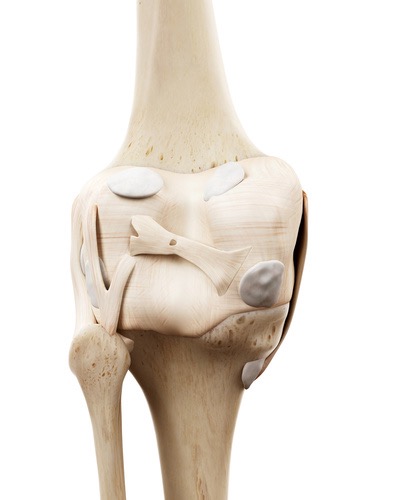

この弓状膝窩靭帯を治療したことはありますか?この靭帯は腓骨頭の外側面から膝窩筋腱を横切って、関節包に付着しています。このように関節包に付着するということは当然関節包に刺激を加え、痛みを生じさせます。そして関節包自体もしくは隣接する膝窩筋に対しても滑走性の低下、筋高度を高めてしまいます。膝痛の最終調整には欠かせない靭帯調整リリーステクニックとなります。

この弓状膝窩靭帯リリーステクニックを学ぶことであなたは、、、

ハンター管症候群(伏在神経麻痺)をご存知ですか?「ハンター管症候群」とは、聞きなれない疾患名ですが、まれに膝から下のふくらはぎの内側当りが痛む、しびれるという疾患があります。大腿神経の枝である伏在神経は内転筋と呼ばれる筋肉の傍を通り、ハンター管(内転筋管)と呼ばれる筋膜の管を通って、さらに下の方へと降りていきます。そして、膝の内側あたりで、膝蓋下枝と、内側下腿皮枝に分かれて、さらに下方へと伸びていきます。

膝~下腿の内側に広がる痛みやしびれは実はこの伏在神経由来の症状であることもあります。よく見逃されがちなところです。

この伏在神経のリリーステクニックを学ぶことであなたは、、、